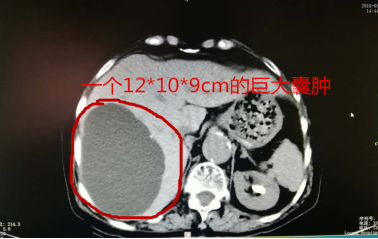

肝里有個(gè)“大芒果”!三個(gè)小孔解決老奶奶的“腹痛”煩惱!

劉奶奶近大半年在勞作時(shí),上腹部就會(huì)出現(xiàn)脹痛的感覺,特別是彎腰時(shí)更為明顯,這真是讓人莫名其妙且苦惱!